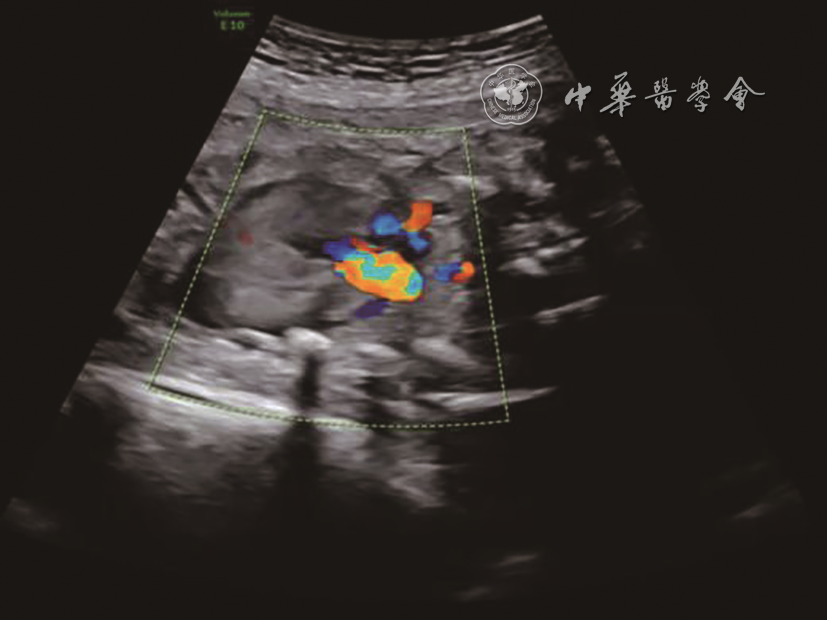

From July 2018 to May 2019, 12 fetuses were diagnosed with pulmonary atresia with intact ventricular septum (PA/IVS) with right heart dysplasia and treated at the Women and Children's Hospital, Qingdao University. The median gestational age was 27 (26-28) weeks. All fetuses underwent FCI under the guidance of echocardiography. Our experience with the application of perioperative echocardiography in FCI was then summarized.

All fetuses in this study underwent FCI successfully, with an average operation time of 5.3±1.11 min. Bradycardia occurred immediately after FCI in 5 fetuses, which needed to be treated with epinephrine or atropine in the right atrium. A small amount of pericardial hematocele can be absorbed by the fetus in the early stage after FCI. One mother each chose to terminate pregnancy due to heart failure and due to right ventricular dependent coronary circulation. Finally, 10 fetuses were born alive, and most fetuses needed intervention again after birth, and achieved biventricular circulation.

Echocardiography plays an important role in preoperative indication evaluation, intraoperative guidance, and postoperative observation of FCI. Standardized operation is the key to ensuring the success of FCI.